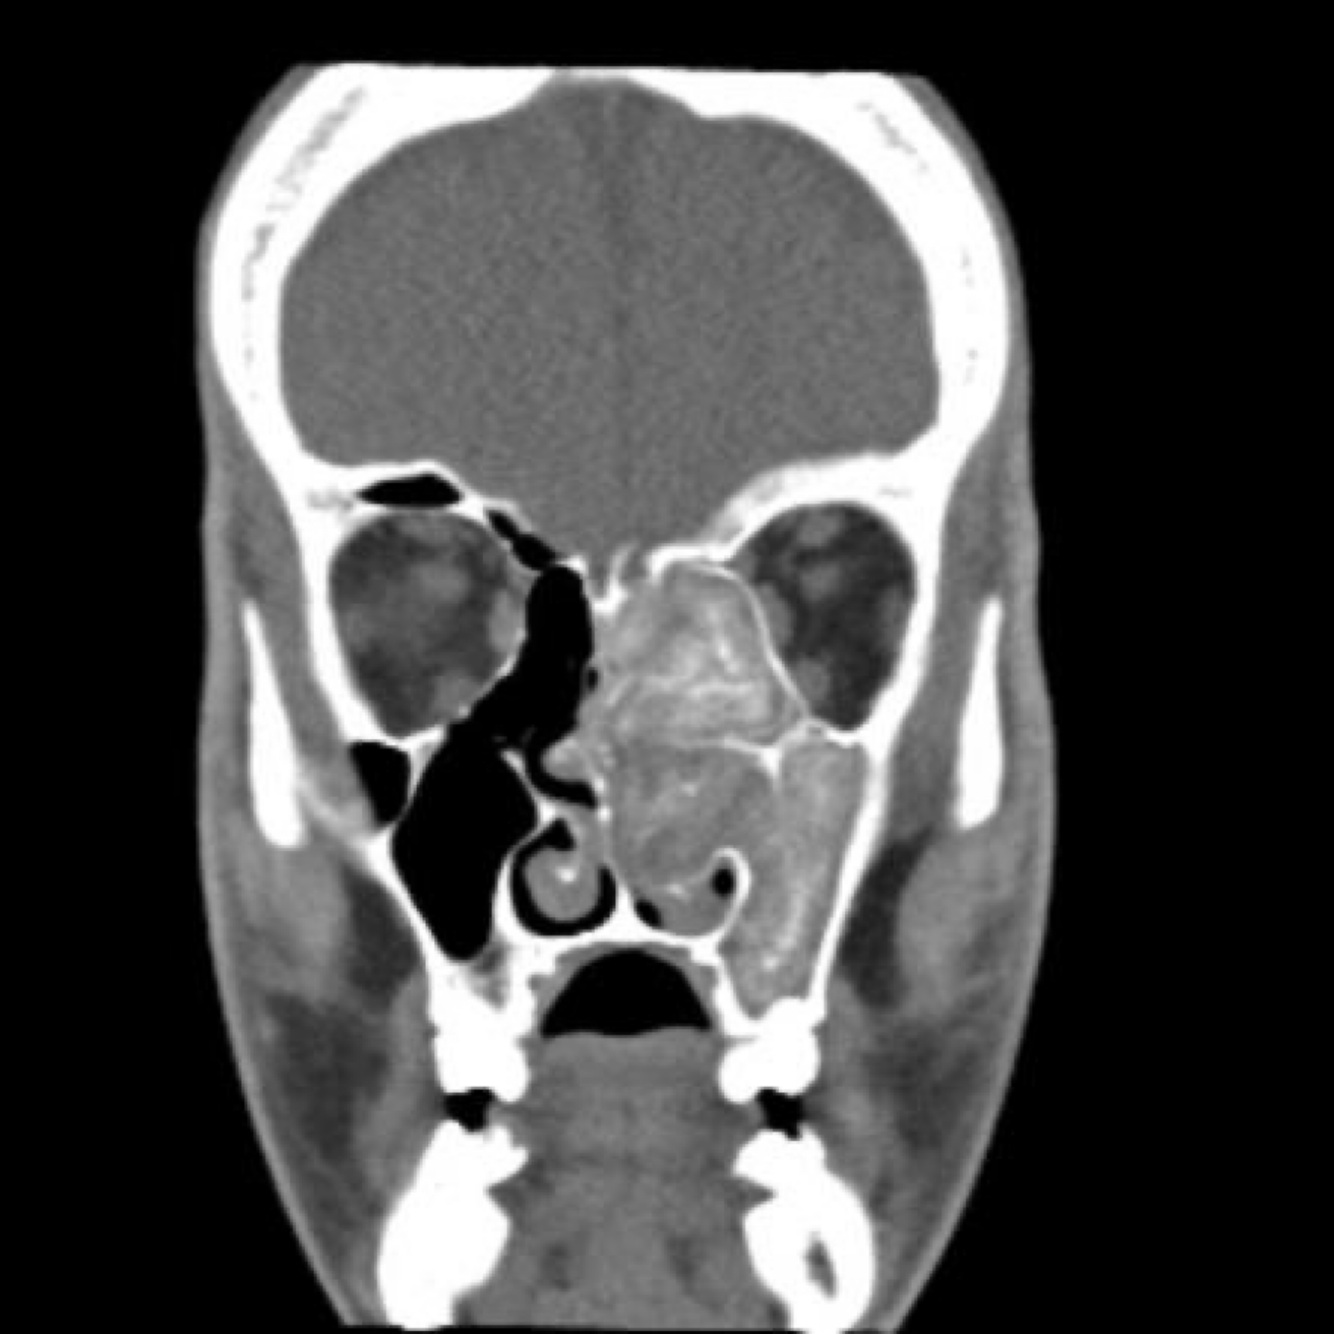

A 69-year-old female presents with nasal obstruction, facial pressure and discolored nasal drainage for 4 months that is recalcitrant to topical steroid sprays, nasal irrigations, and oral antibiotics.

Diagnosis?

A

Inverted papilloma with a bony stalk attaching near the infraorbital nerve

What next step would assist in diagnosis?

A biopsy is warranted to confirm the diagnosis, w/use of a bioendoscopy filter.

12

Q

CT of paranasal sinuses reveals erosion or expansion into

lateral nasal wall or extension into maxillary or ethmoid sinuses, and may reveal calcifications.

Inverted Papilloma.